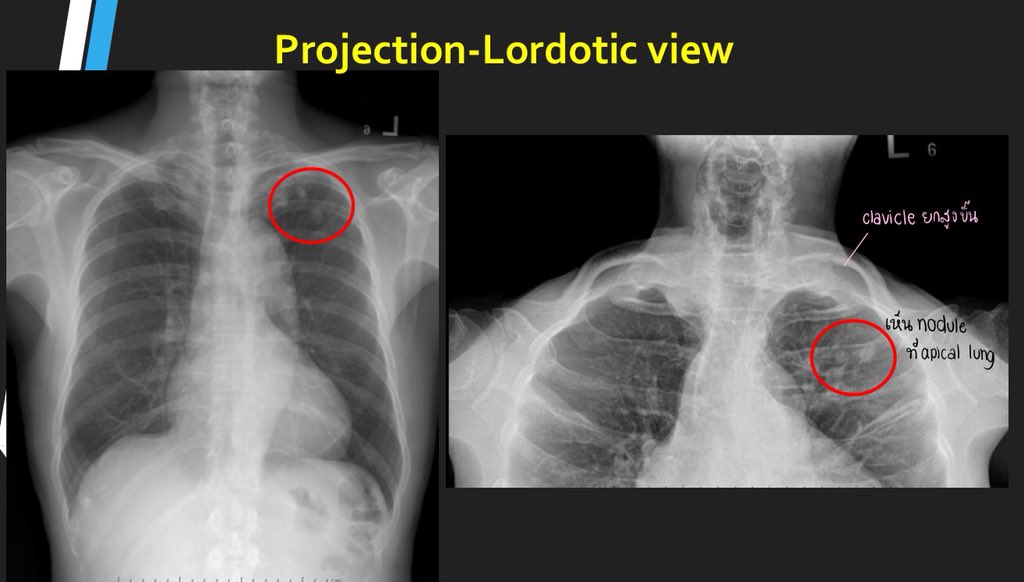

The ap lordotic projection is often used to evaluate suspicious areas within the lung apices that appeared obscured by overlying soft tissue, upper ribs or the clavicles on previous chest views (e.g. An atheromatous aorta is one that has plaque formation lining the wall of the aorta which is the major blood vessel that leaves the heart. The beat of the heart as felt through the walls of a peripheral artery, such as that felt in the radial artery at the wrist. Ap lordotic chest x ray is primarily to rule out calcifications and masses beneath the clavicles or in the apices of lun… july 27, 2021. Contextual translation of apicolordotic view into tagalog. There are two alarming signs in your case : What is the meaning of faint nodular opacities on apicolordotic view of the chest? Ap lordotic (upright) ap lordotic chest x ray is primarily to rule out calcifications and masses beneath the clavicles or in the apices of lungs.

It is also known as the lindblom method. This could be fluid, possibly from pneumonia, or pulmonary tuberculosis. Dosto aj app sikhne ja rhe hai lordotic view. Usually ap lordotic is taken with a pa or an ap normal chest x ray. It is done to look at the top portion (apex) of lung clearly. An apicolordotic view is an additional view of the lungs usually. I am worried about my sister condition. Apicolordotic view is suggested pneumonia.both parahilar region and right lower lung pleuro diaphagmatic reaction.both hemidiaphragm. The rest of the report you have posted suggests that something (suspicious opacities) are seen in the right lung. Asked for female, 28 years. In cases of tuberculosis or tumor). The ap lordotic projection is often used to evaluate suspicious areas within the lung apices that appeared obscured by overlying soft tissue, upper ribs or the clavicles on previous chest views (e.g. A combining form of apex or apical: